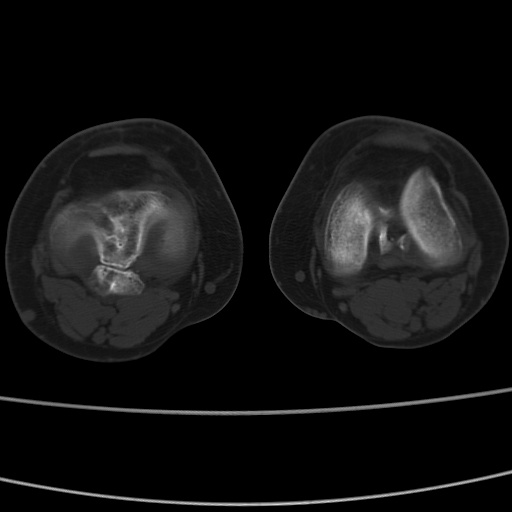

女性,50岁。【请提供患者临床症状体征】

右膝关节退行性改变,关节游离鼠。

右膝关节退行性改变,滑膜黏液囊钙/骨化并游离。

右膝关节退行性改变